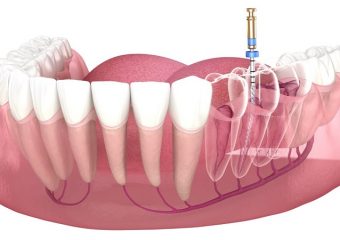

- عصب کشی دندان و درمان ریشه

- مراحل درمان ریشه

- دستیابی به کانال

- تعیین طول کانال

تمیز کردن و شکل دادن کانال ها:

مهمترین فاکتور در درمان، حذف یا کاهش بافت پالپی ملتهب یا نکروز و میکروارگانیسم ها می باشد.

پرکردن کانال:

هدف از پر کردن کانال، به وجود آوردن یک مهر و موم کامل در تمام طول سیستم کانال ریشه از مدخل تاجی تا انتهای اپیکال می باشد.